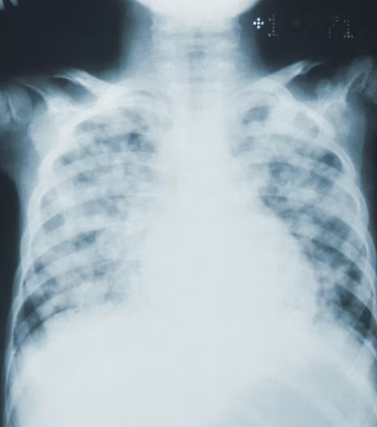

간 질환

간은 오른쪽 갈비뼈 바로 아래에 위치한 가장 큰 장기입니다. 간은 '침묵의 장기'라고 불릴 만큼 질환이 상당히 진행되기 전까지는 특별한 증상을 보이지 않는 경우가 많습니다. 하지만 간에 문제가 생기면 오른쪽 갈비뼈 아래 통증을 유발할 수 있습니다.

지방간, 간염(급성/만성), 간경변, 간암 등이 대표적인 간 질환입니다. 간 질환으로 인한 통증은 둔하고 지속적인 경우가 많으며, 피로감, 소화 불량, 황달(피부나 눈이 노랗게 변함), 소변 색 변화, 식욕 부진 등의 증상이 동반될 수 있습니다. 특히 잦은 음주나 비만이 있다면 간 건강에 더욱 주의해야 합니다.